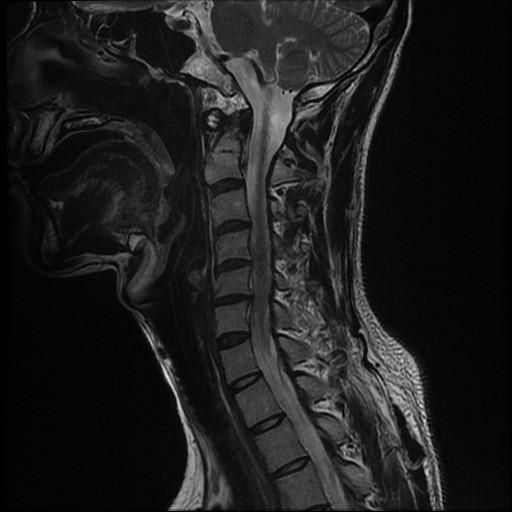

경추MRI사진과 결과지입니다.

결과지에는 디스크라고만 나와있는데

인대골화증이나 척수증은 아닌지 다시 한번 봐주시면 감사하겠습니다.

• 1번 째 사진

사진상으로 보았을때 목 디스크 주변에 염증이 있는 것으로 보이고, 추간판 탈출의 증상이 있는것으로 보입니다. 정확한 상태는 담당 주치의 선생님과 상담 받아 보시면 좋을 것 같습니다.

해당 영상의학적 검진 상 디스크에 대한 진단이 정확해보입니다. 골화증이 될려면 하얗게 생긴 띠 등이 보여야 하지만 그런 증상들이 보이지 않습니다.

일반적으로 디스크 탈출증이나 퇴해성 변화에 관련된 문제 일 수 있습니다.  MRI소견에서 인대 골화증이 의심되는 소견(인대 두께 증가)나 척추 압박이 있는 경우 그에 대한 언급이 있어야 합니다. 결과지를 의사와 상담을 통해 구체적인 진단을 받는 것이 좋습니다!

목 디스크 주변에 발생한 염증이 있는 것으로 보이는데요, 추간판 탈출의 증상이 있으신 것으로 보여집니다. 조금 더 정확한 소견은 전문의와 상담을 해보시는 것이 좋겠습니다.

위의 영상촬영본을 봤을때는 목 디스크 주변에 염증이 있는것으로 보입니다 보통 추간판탈출증(목디스크) 증상이 있습니다 담당의사랑 충분히 상담받으시고 치료계획을 세워보시는것을 권해드리고 다른병원 2군데 정도 더 가보셔서 다른의사의 의견도 들어보는것도 괜찮습니다